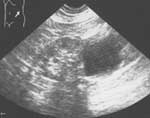

В положении больного на здоровом боку проводится эхоскопия почки. На экран монитора выводится киста (Рис. 1), после чего приступают к выполнению пункции кисты. Все этапы процедуры проводятся под контролем эхоскопии. При использовании ультразвукового пункционного датчика игла продвигается к кисте по направляющему каналу. Момент проникновения иглы в просвет кисты четко фиксируется на экране монитора в виде яркой белой точки или полоски в полости кисты (Рис. 2). При аспирации в шприц начинает поступать содержимое кисты, которая по мере эвакуации содержимого уменьшается в размерах (Рис. 3). После полной эвакуации содержимого из кисты жидкость в ее проекции не определяется и все сегменты почки четко выводятся на экран (Рис. 4). В полость кисты вводится 96о этиловый спирт в объеме равном 50% от объема эвакуированной жидкости и на экране монитора опять появляется скопление жидкости в кисте (Рис. 5 ).

Рис. 1. Эхограмма области левой почки. Сканирование со стороны боковой стенки живота (проекция средней подмышечной линии ниже 12-го ребра). Простая киста почки 122х102 мм. Почка из-за кисты не визуализируется.